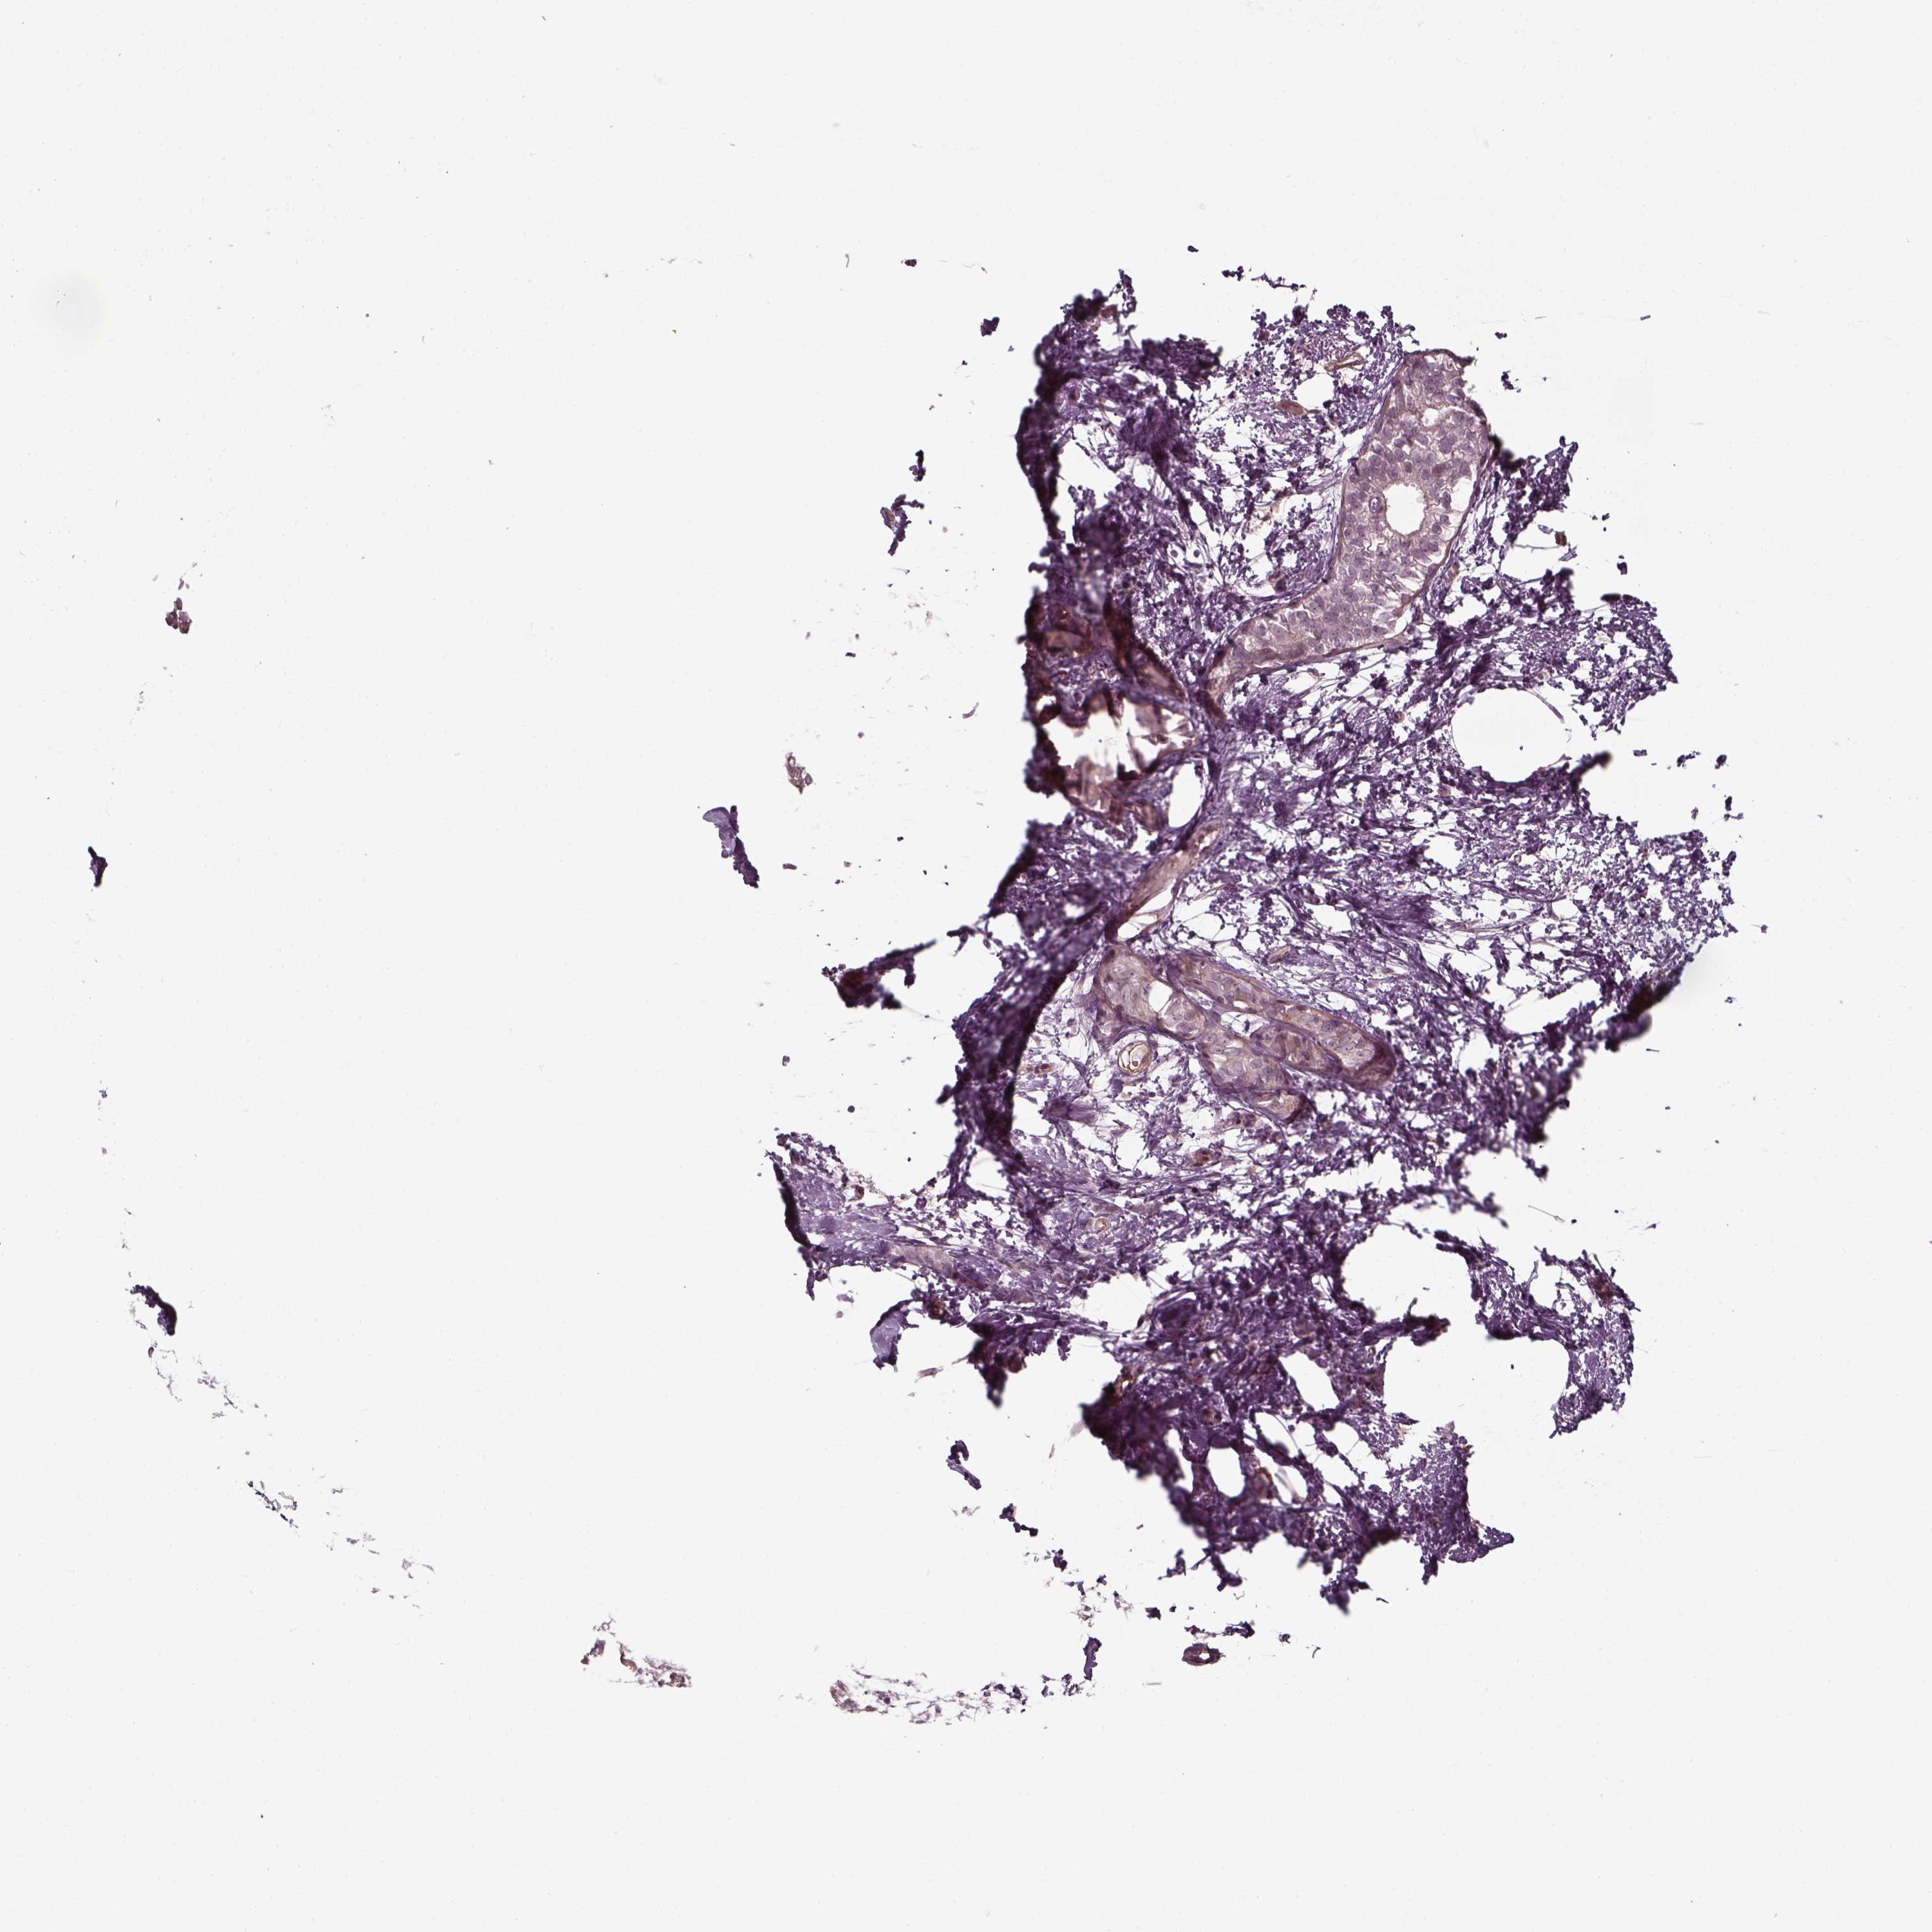

CANCER BREAST CANCER Show tissue menu

BRCA TCGA BRCA VALIDATION PROTEIN EXPRESSION

ANTIBODIES

AND

VALIDATION